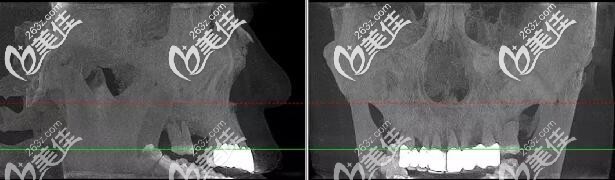

术前肖先生CBCT口腔影像